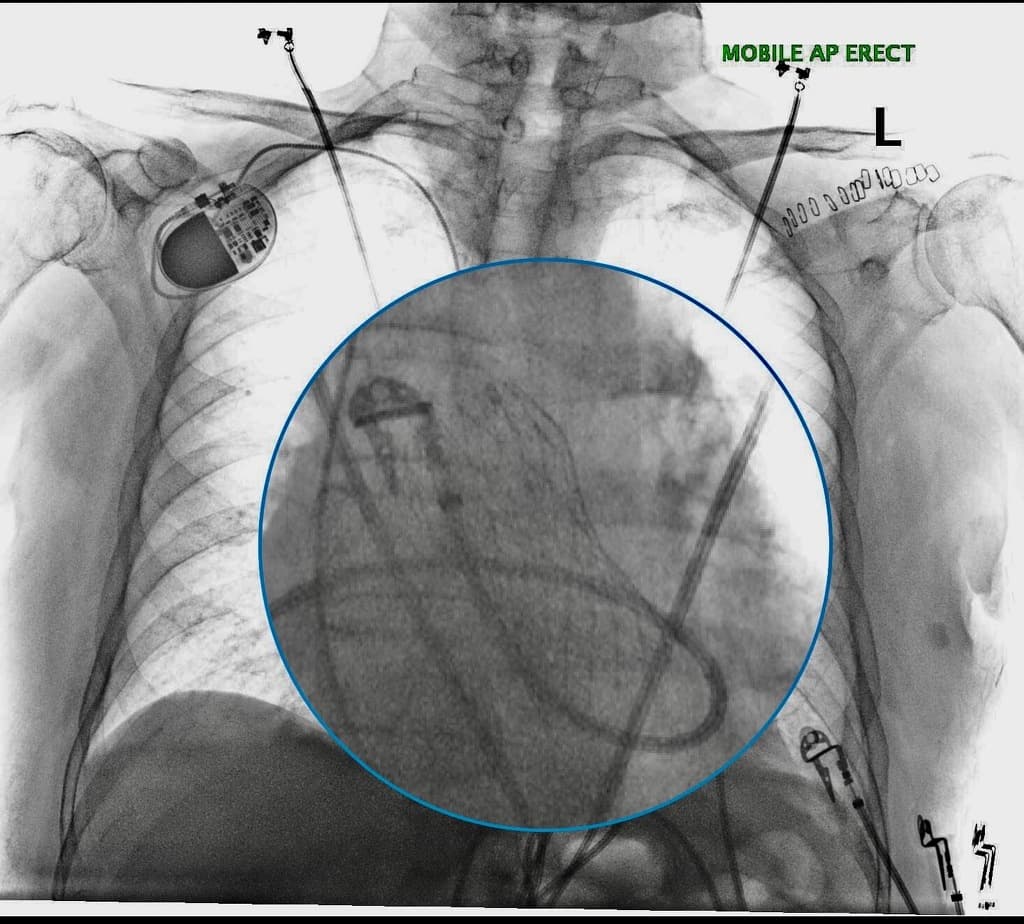

Frontal

X-ray•Frontal•1 Img

- Mở xương ức đường giữa (Median sternotomy).

- Máy tạo nhịp (Pacemaker).

- Thay van động mạch chủ (Aortic valve implantation).

THẢO LUẬN (DISCUSSION): Việc "thay" van này có hình dạng giống "stent" hơn, phù hợp với (consistent with) thay van động mạch chủ qua ống thông (transcatheter aortic valve implantation). Ngày càng có nhiều trường hợp này được quan sát thấy trên phim X-quang quy ước (plain radiograph).

Thay van động mạch chủ qua ống thông (Transcatheter aortic valve implant)

- "Khớp giả TAVI/TAVR được đặc trưng bởi khung kim loại dạng stent cản quang có thể thấy trên X-quang quy ước."

- "Thiết bị thường được đặt ở mức vòng van động mạch chủ, vị trí này thấp hơn và đứng dọc hơn so với van động mạch phổi."

Thay van động mạch chủ qua ống thông (TAVI), còn được gọi là TAVR, là một thủ thuật ngày càng phổ biến để điều trị hẹp van động mạch chủ có triệu chứng. Trên chẩn đoán hình ảnh, khớp giả xuất hiện dưới dạng cấu trúc dạng stent riêng biệt, giúp phân biệt với các vòng khâu thường thấy trong thay van động mạch chủ qua phẫu thuật truyền thống (SAVR). Trong trường hợp này, sự hiện diện của đường mở xương ức giữa gợi ý tiền sử phẫu thuật tim trước đó, trong khi máy tạo nhịp cho thấy việc quản lý hệ thống dẫn truyền, vốn là một yêu cầu tiềm tàng sau các can thiệp van tim. Việc nhận biết hình ảnh X-quang của TAVI là rất quan trọng để đánh giá vị trí thiết bị và các biến chứng tiềm ẩn.